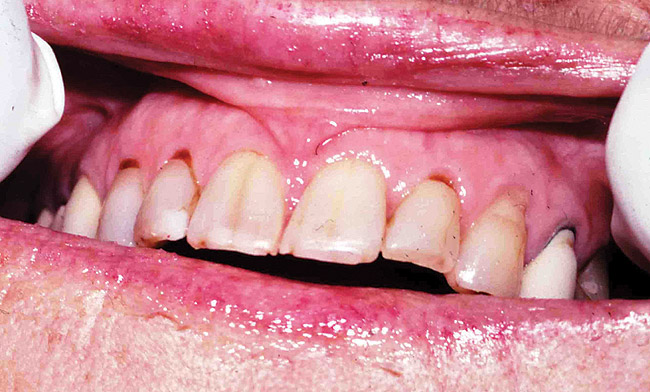

Saliva aids for oral cavity cleansing, swallowing, taste, speech, and digestion could be compromised in patients with salivary gland hypofunction. The oral mucosa may appear dry and friable. The tongue may appear dry and fissured (Figure 1). Dental caries, plaque accumulation, gingivitis, and periodontitis are common in patients with significant salivary gland hypofunction (Figure 2). Infections, such as oral candidiasis (Figure 3), and enlargement of salivary glands from sialadenitis are seen commonly in patients with moderate-to-severe salivary gland hypofunction (Figure 4). Difficulty in mastication and swallowing also may indicate advanced salivary gland hypofunction19 and can contribute to poor nutrition.20 Denture retention may become difficult because of the lack of saliva12 (Table 3).

Figure 2  Dental caries is usually seen in cervical and incisal surfaces.

Figure 2